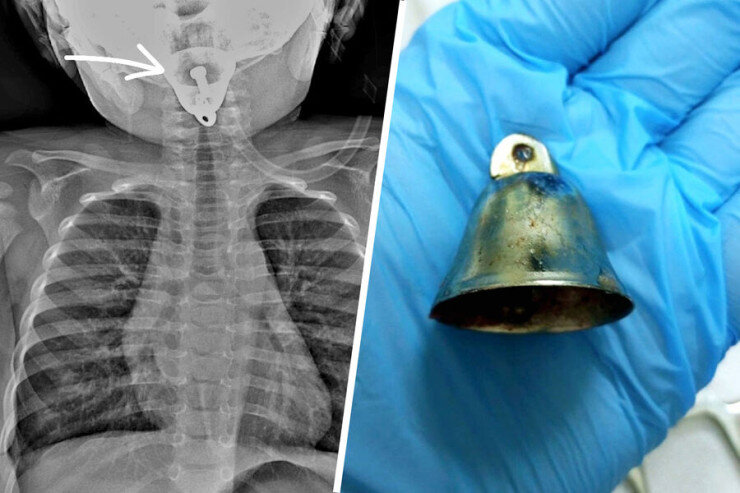

Bir yaşlı uşaq "yolka"nın bəzəyini udduLipetsk Regional Uşaq Xəstəxanasında bir yaşlı uşağın tənəffüs yolundan metal zəng çıxarılıb.

Sonxeber.az Lent.az-a istinadla bildirir ki, bir yaşlı uşaq tənəffüs yollarında yad cisim şübhəsi ilə Lipetsk uşaq xəstəxanasına aparılıb.

Xəstəxananın baş həkiminin sözlərinə görə, valideynlərin bir neçə dəqiqə diqqətsizliyinə görə uşaq Yeni il bəzəyi olan metal zəngi udub. Yad cisim cərrahlar tərəfindən çıxarılıb, zərərçəkənin həyatı və sağlamlığı üçün təhlükə yoxdur.